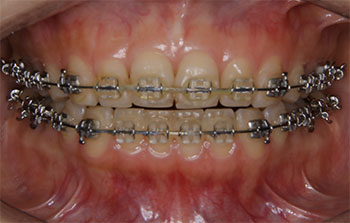

2)あごの発育が終了した人の場合 (Ⅱ期治療)

マルチブラケット装置などを用いて全顎的な歯の移動を行います。